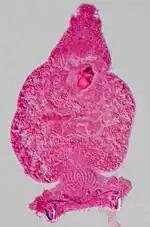

Les organes, trop gros pour laisser passer la lumière nécessaire à la microscopie optique, doivent encore être découpés en lamelles extrêmement fines par un appareil appelé microtome. Pour cela, on les enrobe dans de la paraffine ou une résine, selon l'épaisseur souhaitée de la coupe. On distingue plusieurs types de coupe selon la méthode de conservation et d'amincissement suivie :

| Conservation | Inclusion | Épaisseur de la coupe |

|---|---|---|

| Congélation (à −20 °C) | OCT | 5 à 100 μm |

| Polymérisation des protéines | Paraffine | 5 μm |

| Polymérisation des protéines et lipides | Résine | 1 à 0,05 μm |

Les coupes de 0,05 μm seront analysées en microscopie électronique tandis que les autres seront observées en microscopie optique.

Coloration

Les tissus biologiques présentent en eux-mêmes très peu de contraste, aussi bien en microscopie optique qu’en microscopie électronique. La coloration est utilisée aussi bien pour augmenter le contraste que pour mettre en valeur l’une ou l’autre structure en particulier.